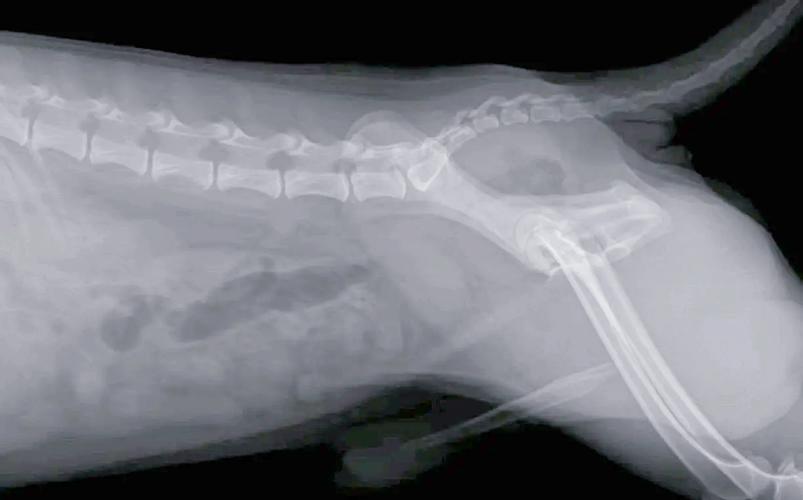

术前禁食禁水 禁食:通常需要在检查前8『1』两小时停止喂食,以确保胃部排空,便于医生观察。禁水:在检查前2『4』小时停止饮水,具体时间需遵医嘱。 术前检查 确保狗狗进行必要的术前检查,如血液检查、X光或超声波,以评估狗狗的整体健康状况,排除潜在风险。

狗狗拍一个x光片多少钱一般宠物医院的标价在80『1』20元/体位/张,比如胸部,腹部,腿部这样区分,通常为了确诊,同样的部位会拍两个体位,也就是160『2』40元。人去的当然不能让狗进啦,避免交叉感染嘛。正规的宠物都可拍片,拍片的费用在60至80元。那么狗狗做B超一般多少钱。其实B超的费用并不是很贵,甚至比拍片还要便宜一些。

狗狗拍片费用通常在200『8』00元,具体费用受拍摄部位、医院等级及地区差异影响。复杂病例需CT/MRI检查时费用可达2000元以上。基础费用构成 检查类型 (1)常规X光:单次拍摄200『4』00元,适用于骨折筛查、异物定位。